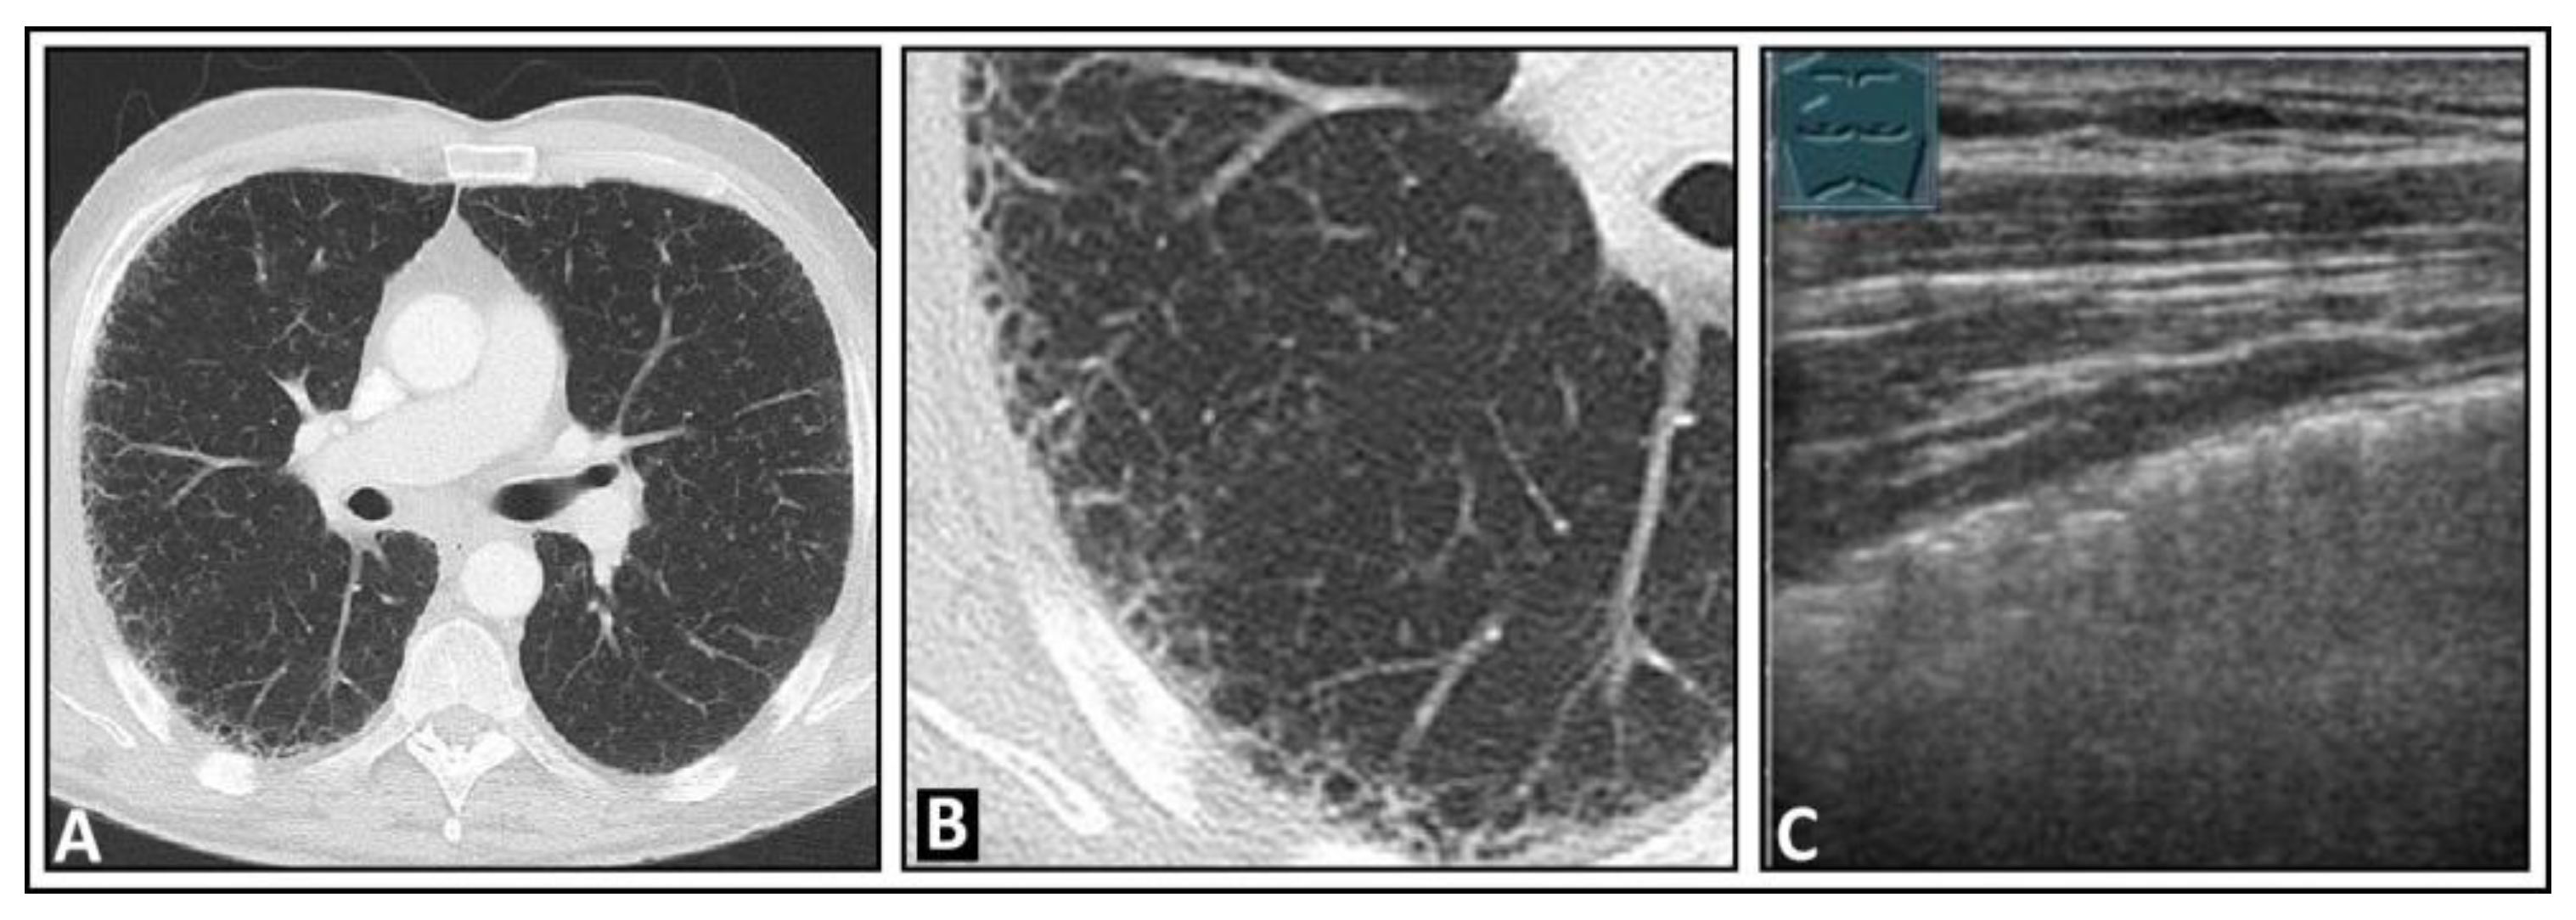

6. Interstitial Lung Disease